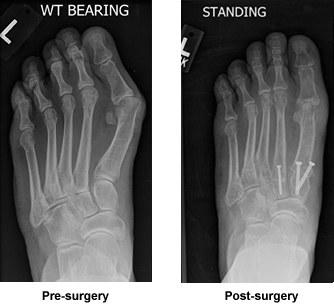

Forever Grateful for Bunion Surgery

I suffered for many years with a bunion along with other issues in my left foot. From the first visit I knew I was with the right doctor. The surgery was successful and I am looking forward to enjoying long walks pain free.